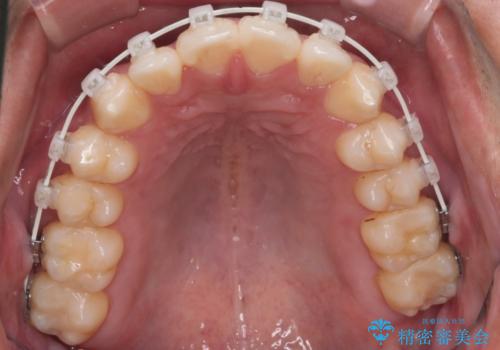

- 矯正装置

- 審美装置

IPR(歯と歯の間を削る処置)と顎間ゴムを行い歯並びを整える治療計画を立てました。

早く終わらせたいとの事でしたが、ゴム掛けを頑張っていただいたので

9ヶ月という短い期間で治療が完了しました。

矯正後は保定経過とメンテナンスで経過を見ていきます。